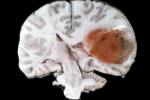

في كانون الثاني 2021، تلقت كيري أخباراً غمرتها بحزن شديد مفادها أنها مصابة بورم في دماغها يبلغ حجمه 5×5×5 سنتيمتراً.

وبعد أسابيع قليلة، في فبراير (شباط)، خضعت كيري لجراحة "الدماغ المفتوح"، وأُخبِرَتْ أنها مصابة بسرطان دماغي في المرحلة الثانية أدى إلى معاناتها ما يسمى "حبسة الكلام"aphasia  التي تعني مواجهة صعوبة فائقة في الكلام والنطق.